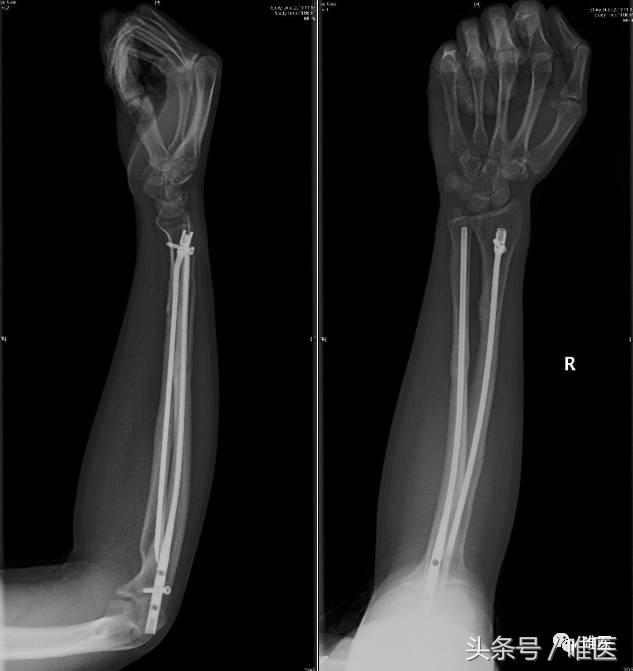

▣ 女性,21岁,右前臂多段双骨折。

▣ 术后正侧位片